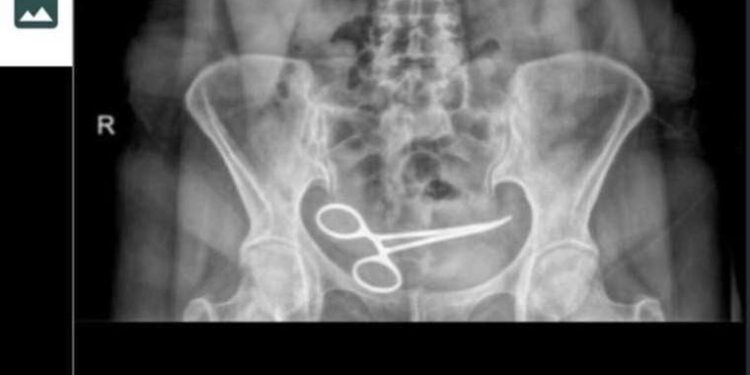

Ankara’da tedavi gördüğü özel hastanede yapılan ameliyattan yaklaşık 8 ay sonra şiddetli karın ağrısı şikayetiyle başka bir hastaneye başvuran Şadiye Boyun’un (54) çekilen röntgeninde karın bölgesinde ameliyat makası olduğu ortaya çıktı. Ameliyat sırasında unutulduğu belirlenen makas, yine ameliyatla alındı. Boyun, ameliyatı gerçekleştiren doktor ve hastane hakkında suç duyurusunda bulundu.

Ankara’da Şadiye Boyun, 28 Aralık 2021 tarihinde Pursaklar ilçesinde, özel hastanede bir kadın hastalığı nedeni ile ameliyat oldu. Ameliyattan 8 ay sonra karın ağrısı şikayeti görülen Boyun, ambulans ile Pursaklar Devlet Hastanesi’ne kaldırıldı. Burada çekilen röntgende Boyun’un ince bağırsağına takılı 12 santim boyunda makas olduğu görüldü. Ardından iddiaya göre, ameliyatın gerçekleştirdiği özel hastaneye haber verildi. Özel hastaneden görevliler geldi.